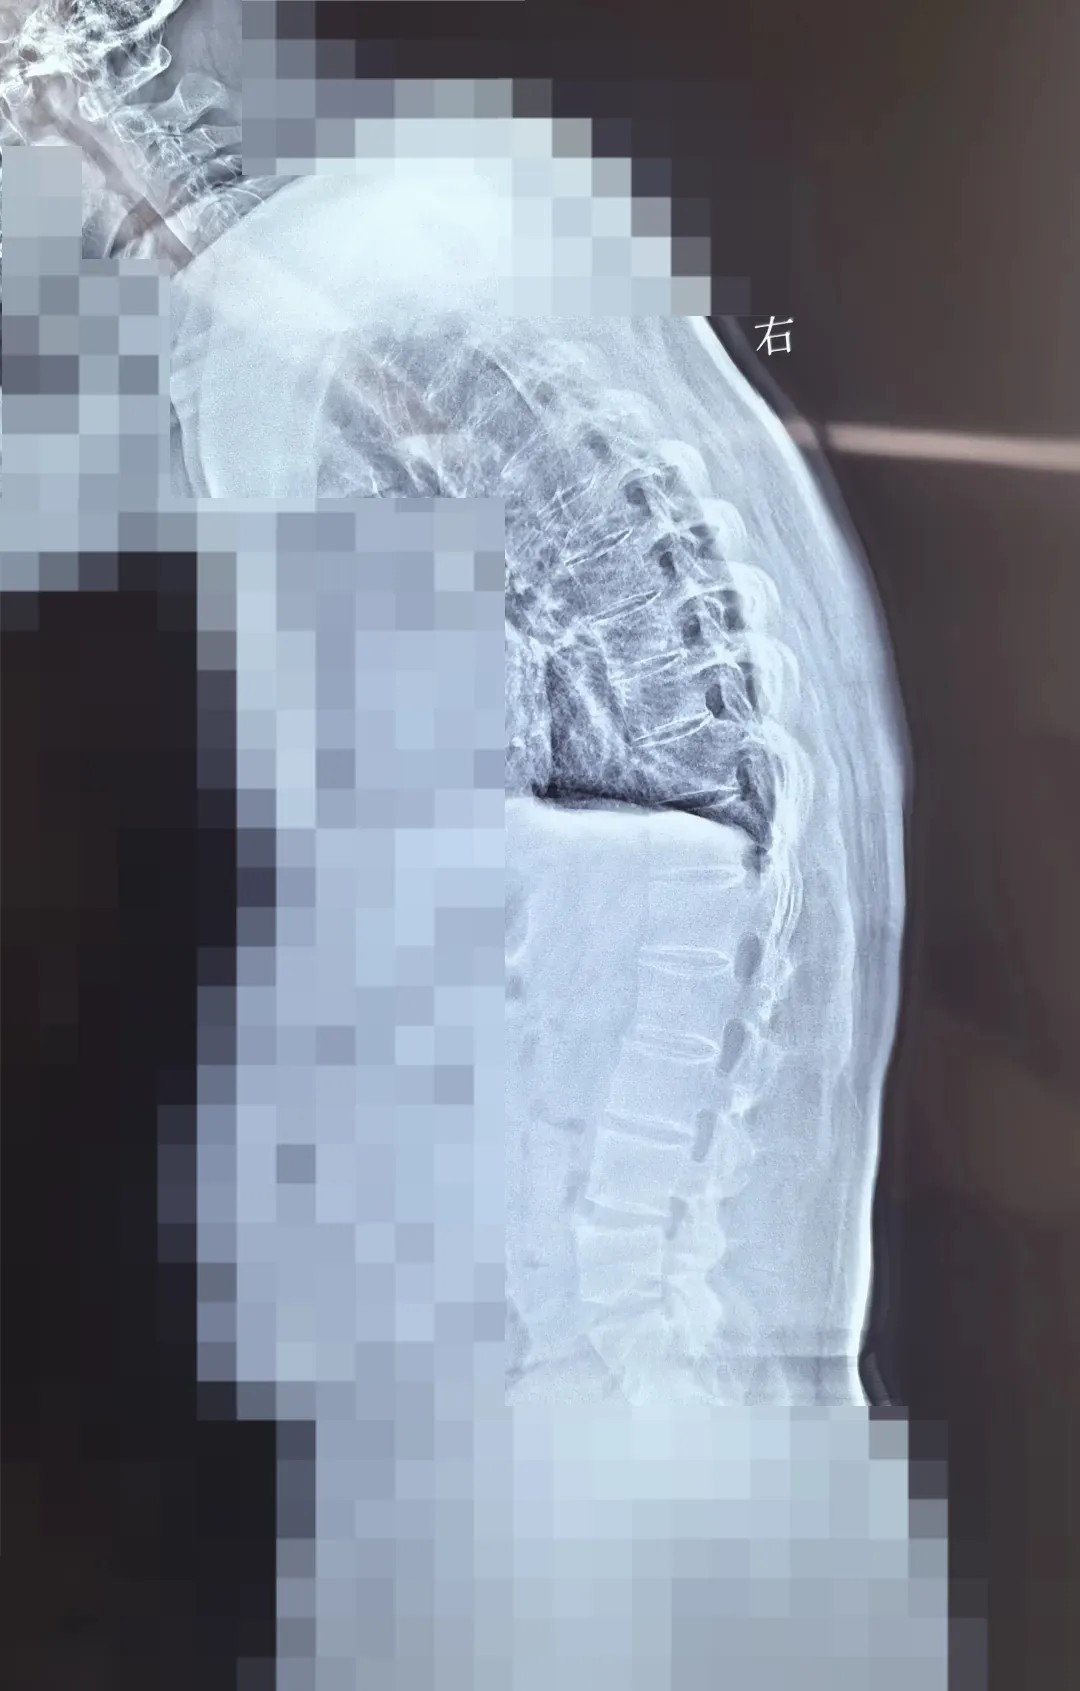

此次手术患者脊柱后凸,外形上看起来弯腰驼背,患者表示自己的视线范围都受影响。普通人可以平视前方,看到的范围较大,这位患者不能平视前方,只能看到自己视线下45度的范围。强直性脊柱炎矫形手术,属于难度大、风险大、复杂度大的骨科手术。此次手术,面临三大核心挑战:

此次手术采用 PSO 截骨 —— 需要将患者病变椎体切除楔形骨块,再通过钉棒系统重新固定矫正。不同于常规脊柱手术,强直性脊柱炎患者因长期炎症导致脊柱 “骨化融合”,手术需面对解剖结构模糊、骨质疏松易骨折等多重风险。无论是截骨、置钉、矫形的哪个环节,都需要精准避开神经与血管,时刻关注脊髓神经的功能状态。